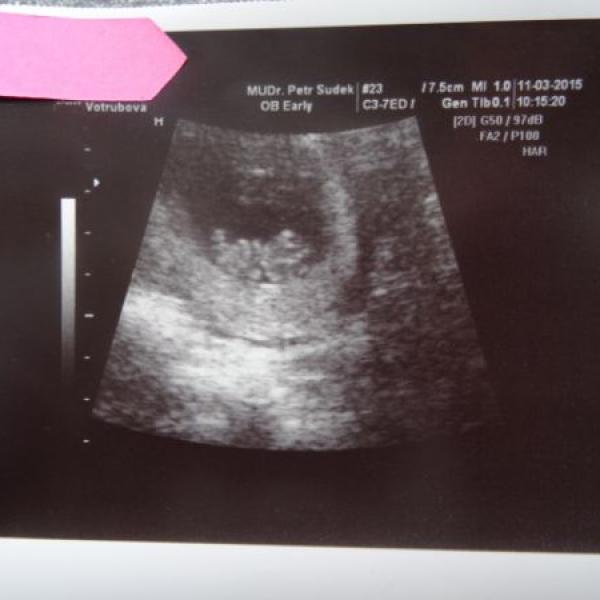

Tak jsem dneska po další kontrole. Vše v pořádku, mimísek krásně prospívá, srdíčko jako zvon, odpovídá 9+2tt a má 2,5 cm. Prý obřík :///: Už se tam krásně mrskal :dance: a prý se předvádí. No vtipný pan doktor. Jinak mám nového gyndaře ve staré ordinaci :) byla jsem z toho paf. Hlavně protože jsem byla u ženský. Ale super příjemný doktor, vše vysvětlil, objasnil, tak že spokojenost.